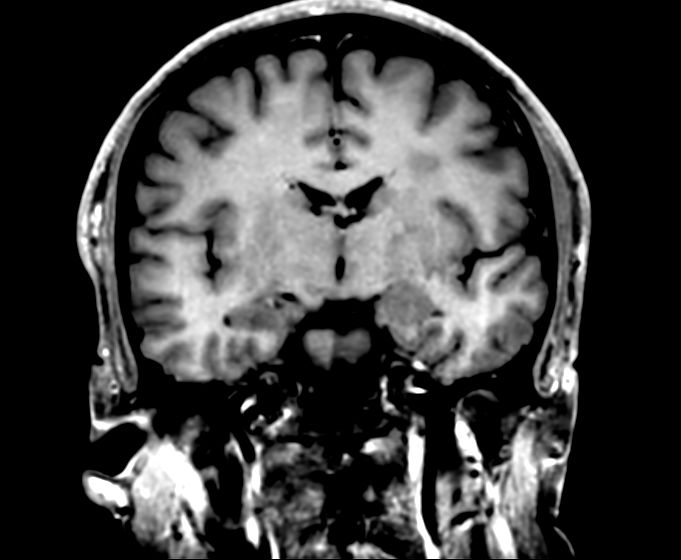

3D VIEW - T1w TSE (coronal reformat)

Pre-Gado

Post-Gado